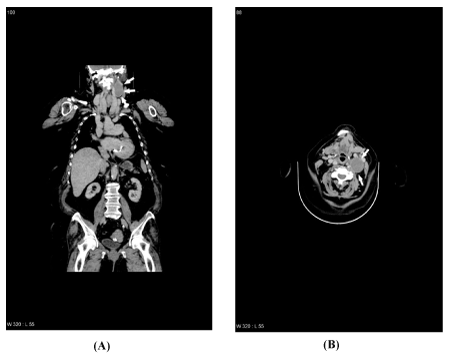

For further characterization of the mass, a contrast-enhanced CT scan was made, which showed a well-circumscribed, oval, hypodense mass with a few calcifications in an irregular border located in level II of the left neck (Figures 1A and 1B). The mass displaced the internal jugular vein anterolaterally and the common carotid artery posteromedially. There was no abnormal cervical lymph node enlargement. The transverse size was 32×37 mm and the craniocaudal dimension was 50 mm.

Figure 1. Contrast-enhanced CT scan (coronal and transversal view) of the neck showing the left-sided vagal schwannoma (white arrows)